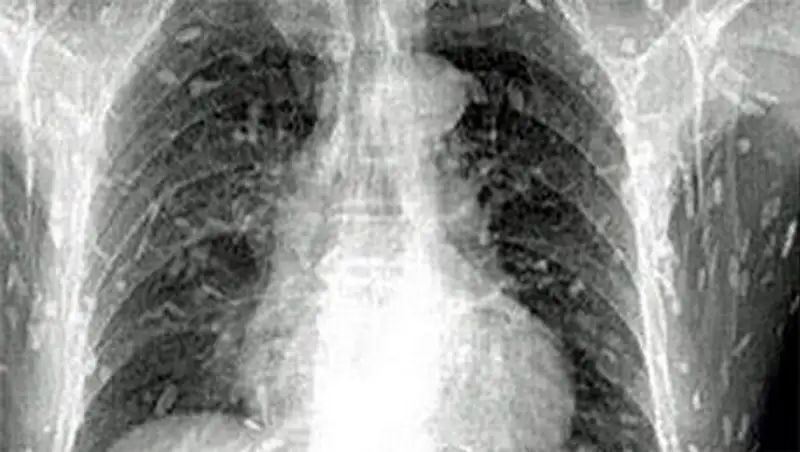

38-летний пациент обратился к врачам с жалобами на потерю веса и тошноту. По его словам, он в течение двух лет испытывал регулярные боли в животе и страдал от анемии.

Медики обследовали его, но первичный осмотр не выявил никаких патологий. Во взятых у мужчины анализах обнаружили яйца бычьего цепня. После проведения медикаментозной терапии пациент избавился от паразита: длина червя достигала 6,2 метра.